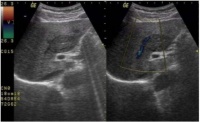

犬猫肝脏疾病的超声临床表现